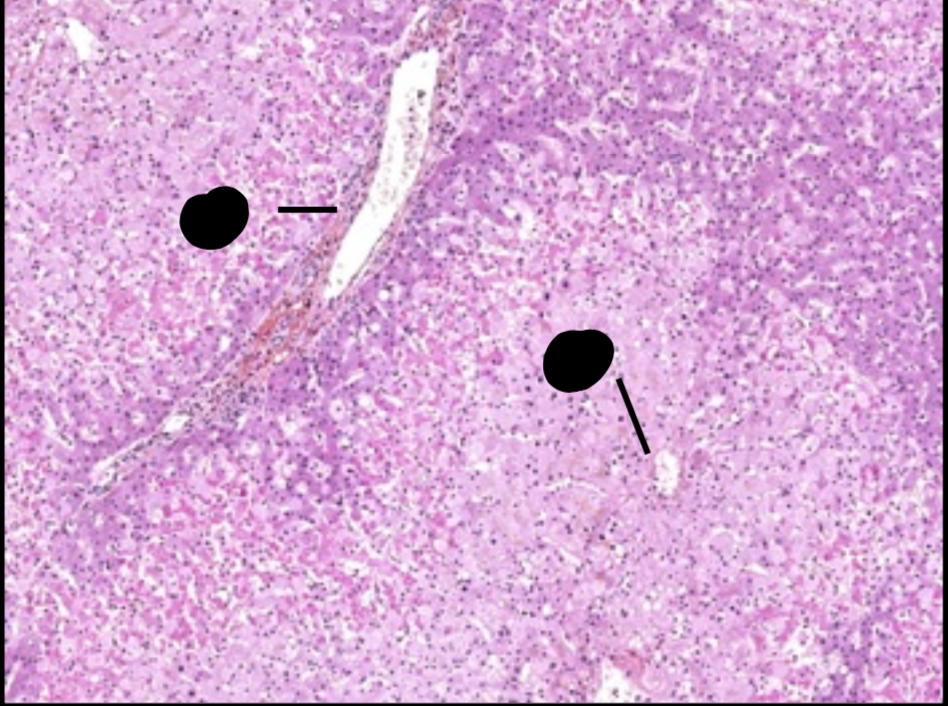

oedème et nécrose du foie

oedème et nécrose cellulaire du foie